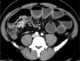

Severe gastric dilatation

Gastric outlet obstruction (GOO) is a medical condition where there is an obstruction at the level of the pylorus, which is the outlet of the stomach. Individuals with gastric outlet obstruction will often have recurrent vomiting of food that has accumulated in the stomach, but which cannot pass into the small intestine due to the obstruction. [Source: Wikipedia ]